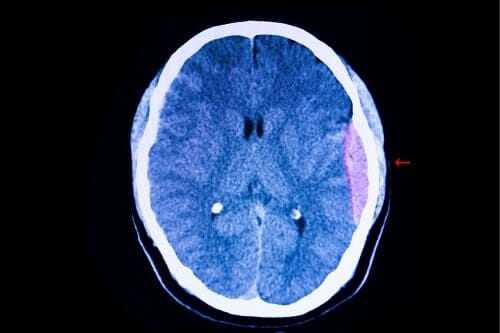

- гематомы внутри мозга, в височных областях, в подкорковых отделах;

Так, при рассеянном склерозе будет отмечаться увеличение межпиковых интервалов I-V, I-III и III-V, а при локальных поражениях ствола (опухоль, гематома), могут наблюдаться изменения межпиковых интервалов в области поражения.

В частности, невринома слухового нерва. Опухоль, даже в начальных стадиях заболевания, может приводить к изменениям на больной стороне. Меняются временные характеристики I-III пиков АСВП, снижается соотношение амплитуды V/I. В таких случаях показано МРТ или КТ исследование. Оно позволяет подтвердить или опровергнуть предположение о наличии невриномы.

ЧМТ легкой степени не будет давать аномальных признаков со стороны АСВП. В результате средних и тяжелых ЧМТ, вызванные потенциалы могут регистрировать отклонения. Нарушения вызываются как первичным поражением ствола, так и вторичными причинами (сдавление отеком, гематомой).

Субарахноидальные кровоизлияния травматического и нетравматического генеза могут приводить к увеличению латентного времени II-V пиков и увеличению межпикового интервала I-III.